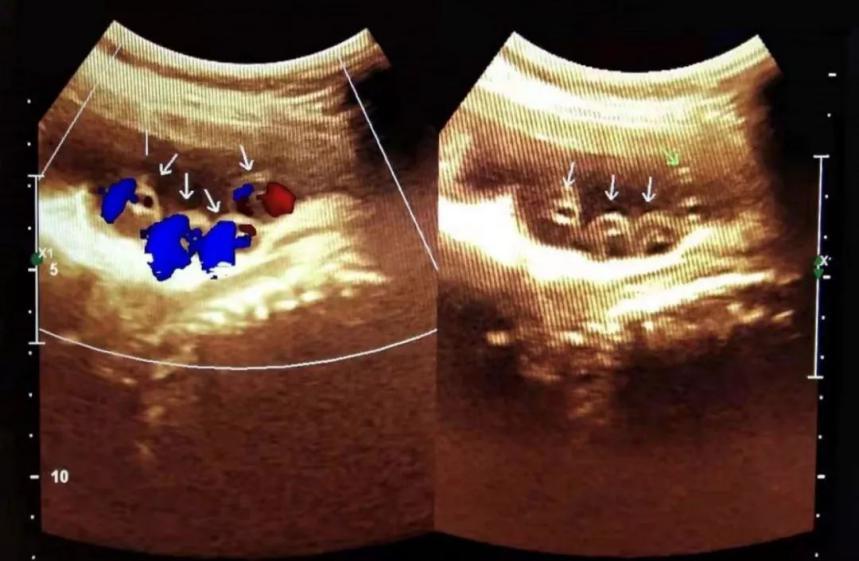

超声,是一种最为简单有效的检查方法。脐带绕颈时在超声中可显示为颈部皮肤压迹,脐带缠绕1周者为U形压迹,缠绕2周者为W形,缠绕3周或以上则为锯齿状压迹。当脐带缠绕过紧时会影响脐带血流通过,超声检测脐动脉血流S/D值或大脑中动脉血流S/D值、胎心监护、计数胎动次数也可以帮助我们了解宝宝有没有出现胎儿缺氧的情况。